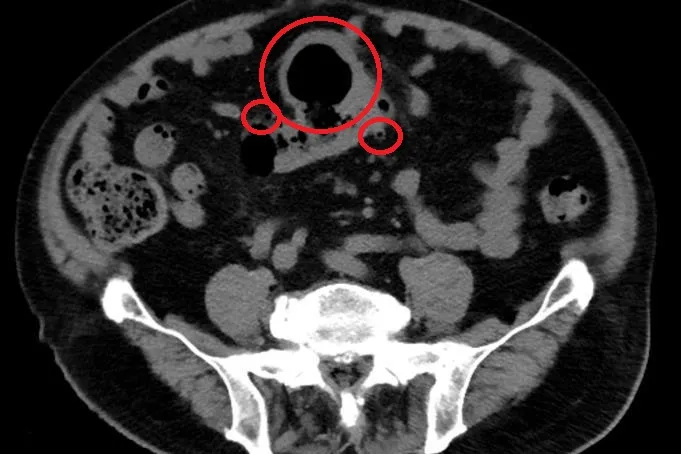

大腸直腸外科醫師陳信宏指出,從電腦斷層發現,趙先生的大腸有多處憩室,合併乙狀結腸有一個巨大囊狀腫塊,甚至產生腹水,其中產生的憩室最大也已至7-8公分,經檢體取樣排除惡性腫瘤的可能後,以微創腹腔鏡手術切除乙狀結腸,5天後趙先生平安出院,不再腹痛。

陳信宏指出,平時經常性攝取高油、低纖食物、抽菸喝酒的人,出現「大腸憩室炎」的機率也越高,通常伴隨腹痛、腹瀉甚至產生血便。臨床上會透過電腦斷層、大腸鏡檢查病患是否有大腸憩室,但大腸鏡為侵入性檢查,不適用於已知腸道發炎的病人,以免發生穿孔的問題。